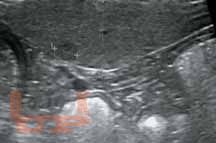

Книга восполняет острый дефицит в учебной литературе по УЗИ мелких домашних животных (кошек и собак). В ней систематизированы и стандартизированы УЗИ почек и мочевыводящих путей, печени и желчевыводящей системы, поджелудочной железы, желудочно-кишечного тракта, сосудистых аномалий брюшной полости (портосистемных шунтов и др.). Приведена методика обследования животных, критерии ультразвуковой нормы и патологии, которые могут быть использованы в протоколах и заключениях УЗИ.

Данное издание обобщает опыт отечественных и зарубежных специалистов. Представлены как собственные исследования авторов, так и материалы из иностранных источников. Текст сопровождается более чем 300 эхограммами.